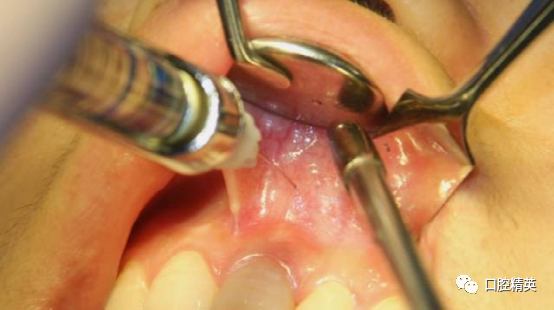

麻醉(唇系带同期修整)

改良梯形瓣切开,范围要充分